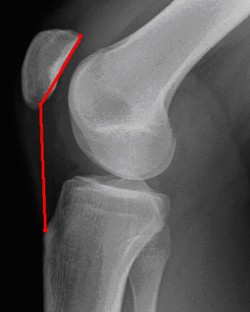

Abb. 6